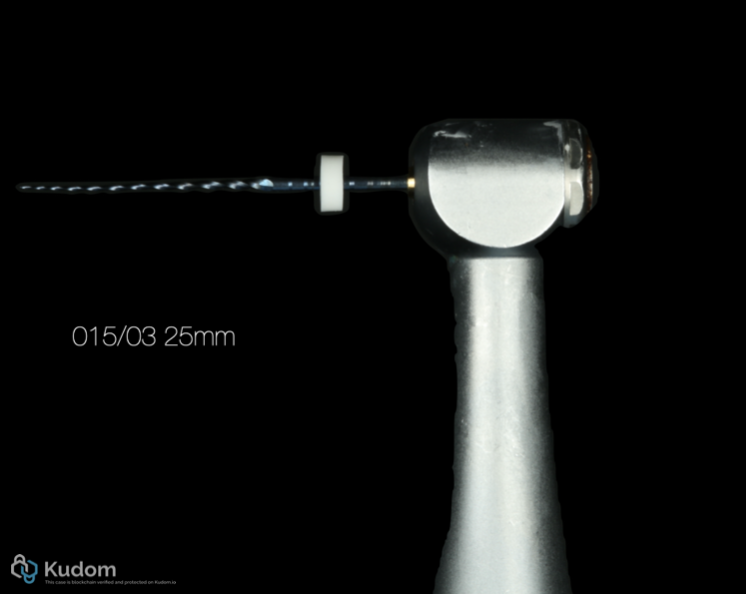

Fig. 12

Assorted file: 15/03 - 25mm